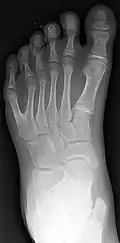

It is associated with at least 39 genetic mutations.[4] It may either present alone or with other defects.[2] Cases may run in families.[2] The underlying mechanism involves an error in limb bud formation during early development.[1] Diagnosis may occur before birth via prenatal ultrasound as early as nine weeks.[2] X-rays may be useful after a child is a year old.[3] The opposite is oligodactyly (fewer fingers or toes).

Classification is performed by using x-ray imaging to see the bone structures.[17] In 1961, Frantz and O'Rahilly proposed that congenital anomalies of the limb could be classified in seven categories, based on the embryonic failure causing the clinical presentation. These categories are failure of formation of parts, failure of differentiation, duplication, overgrowth, undergrowth, congenital constriction band syndrome, and generalized skeletal abnormalities.[36] In 1976 this was modified by Swanson.[37] Polydactyly belongs to the category of duplication.[12] As of 2009, research has shown that the majority of congenital anomalies occur during the 4-week embryologic period of rapid limb development.[12]